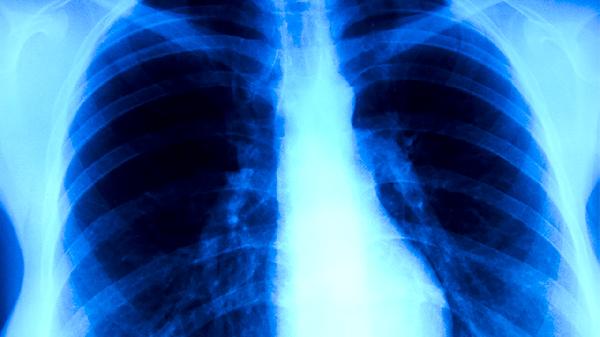

胸部CT是肺癌筛查的首选方法,能清晰显示肺部结节或肿块的形态、大小及位置,对于早期发现微小病灶有较高敏感性。薄层CT扫描可进一步评估病灶边缘特征,如毛刺征、分叶征等恶性征象。增强CT则有助于判断纵隔淋巴结转移及血管侵犯情况。部分医院采用低剂量CT进行高危人群筛查,如长期吸烟者或家族史人群。